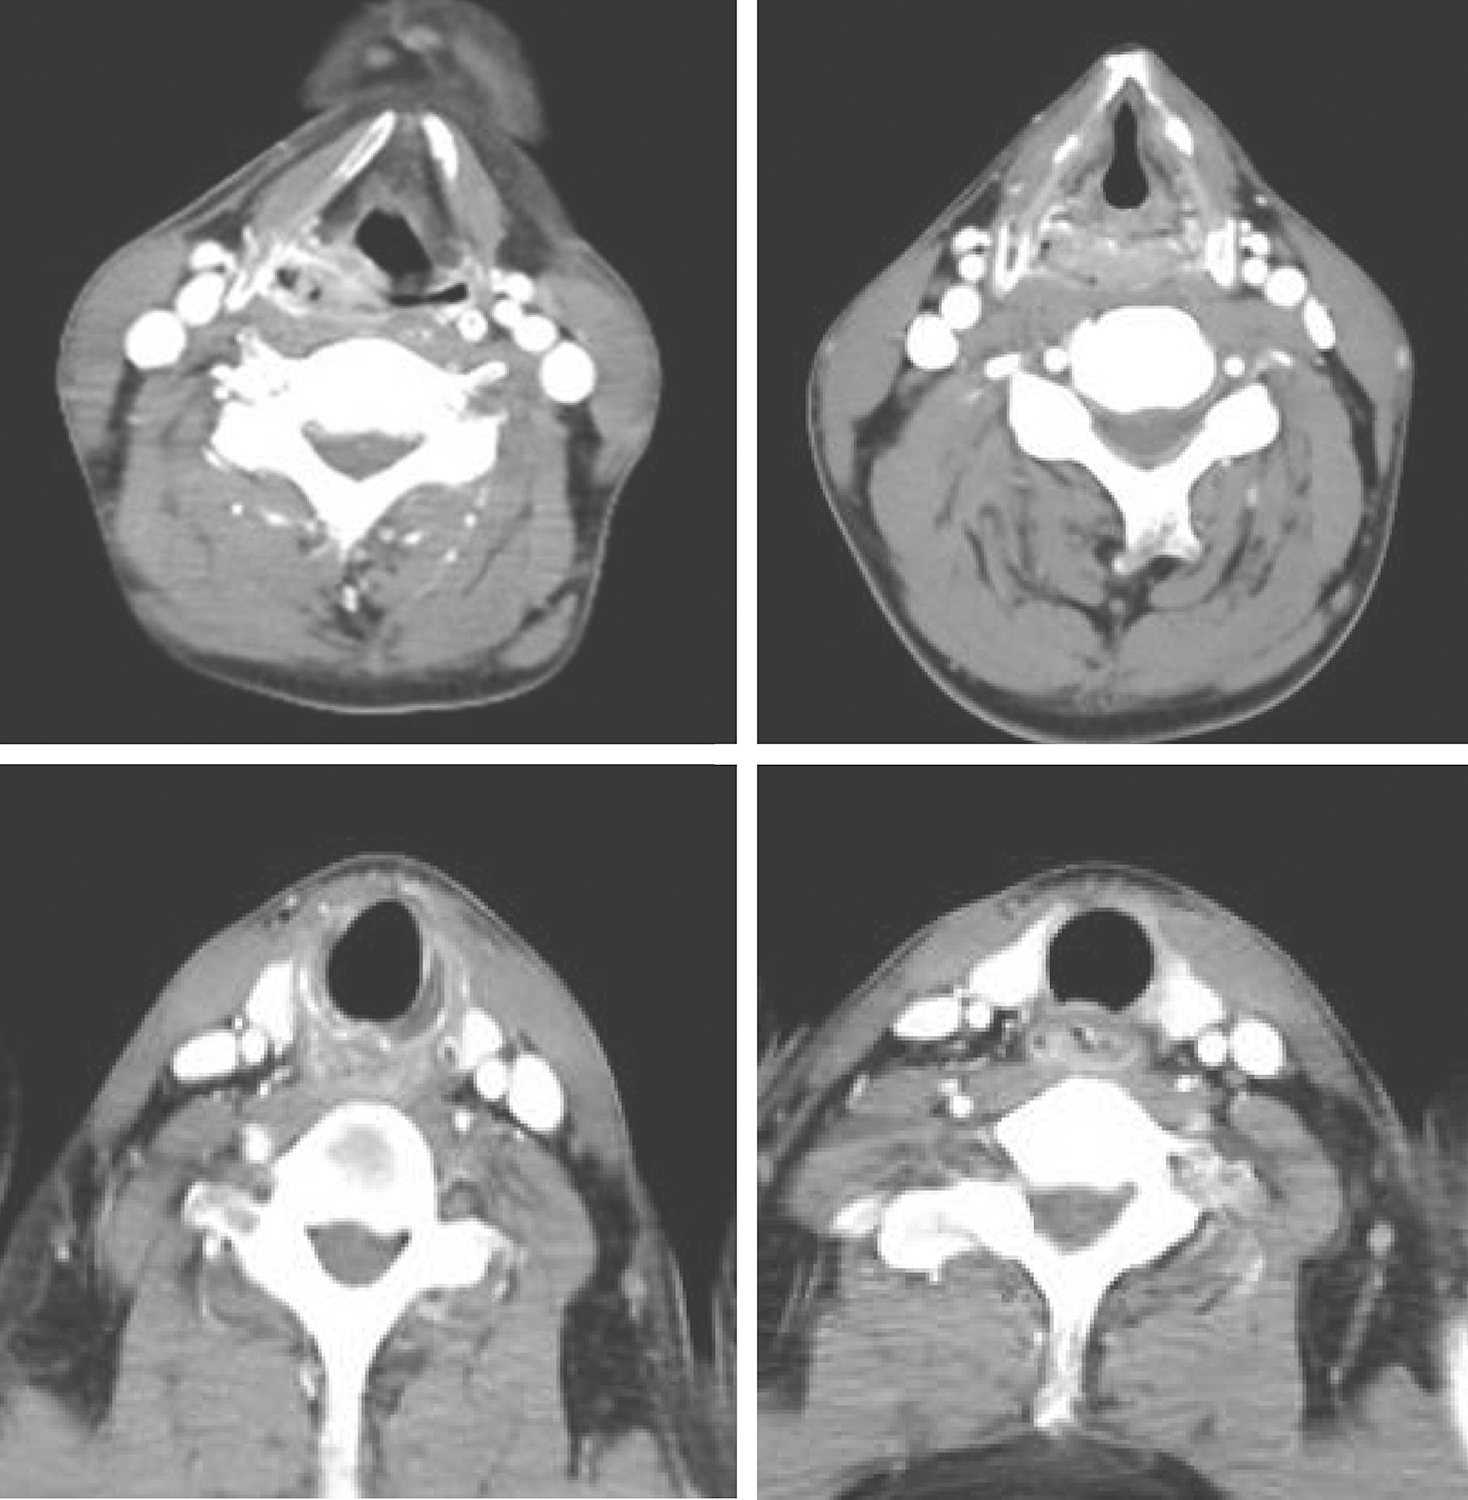

3.2016年7月6日颈胸部强化CT

环后区软组织密度影,强化明显,肿瘤累及双侧梨状窝、向下至颈段食管(图2)。双侧颈部见散在淋巴结,无明显强化。

图2颈胸部增强CT示下咽环后区软组织密度影

符合下咽癌累及颈段食管,双侧颈部散在淋巴结肿大。